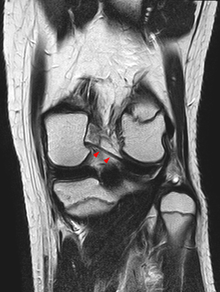

| Posterior meniscofemoral ligament on MRI, coronal |

| Posterior meniscofemoral ligament (Wrisberg) behind the posterior horn of the lateral meniscus close to its insertion. Sometimes wrongly interpreted as a meniscal tear. |

So in the sagital plane, posterior to the posterior horn of the lateral meniscus, we have two structures which could make confusion with posterior horn tear of the lateral meniscus, these two structures are the tendon of popliteus muscle which appears as vertical linear hypo intense structure posterior to posterior horn, while the second one is posterior menisco-femoral ligament.